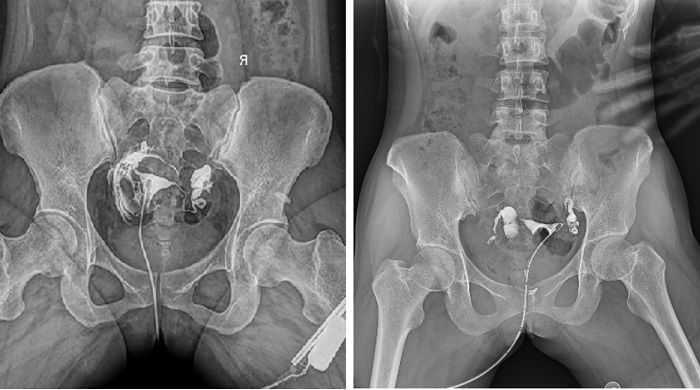

相较于传统胃肠机,动态DR矩形采集面积大,一次曝光即可显示整个盆腔,大幅减少观察时间,可控的瞬时照射避免受检者吸收过多的X线,对育龄期女性的检查尤为重要。毫秒级时间内高清点片,可以在造影剂流动的过程中完成拍片,抓拍到关键图像,更加清楚地了解到管腔的具体通畅情况及堵塞部位,对检查及诊断有非常重要的价值。

子宫输卵管造影

此外,应用动态 DR 进行子宫输卵管造影,还可以在加压推注下,使部分输卵管轻、中度堵塞的患者得以通畅,起到一定的治疗作用。

动态DR依托于可视化点片以及超大高清幅面等先进功能,可应用于多种不孕等妇科检查。目前在国内外医疗机构中,使用动态DR进行子宫输卵管造影是检查子宫输卵管炎的主要方法,同时还有分离粘连的治疗作用,一举两得。不可否认,多功能动态DR的出现,使得妇科造影检查水平得以进一步提高。